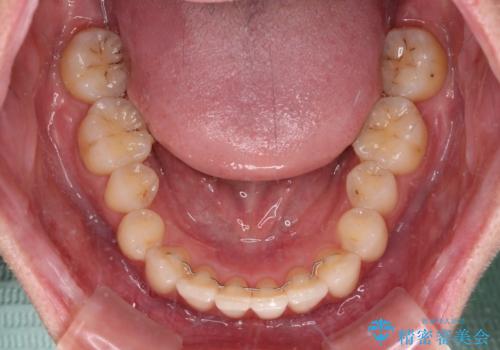

- 前歯のデコボコと強い咬みしめを気にして来院された患者様です。

インビザラインを用いて、前歯の叢生を解消するとともに、ディープバイトを改善していくこととしました。

海外へ転居する予定があったため、1日22時間以上の装着時間をしっかりと守っていただき、予定期間よりも早く、思っていた以上にきれいに仕上げることができました。